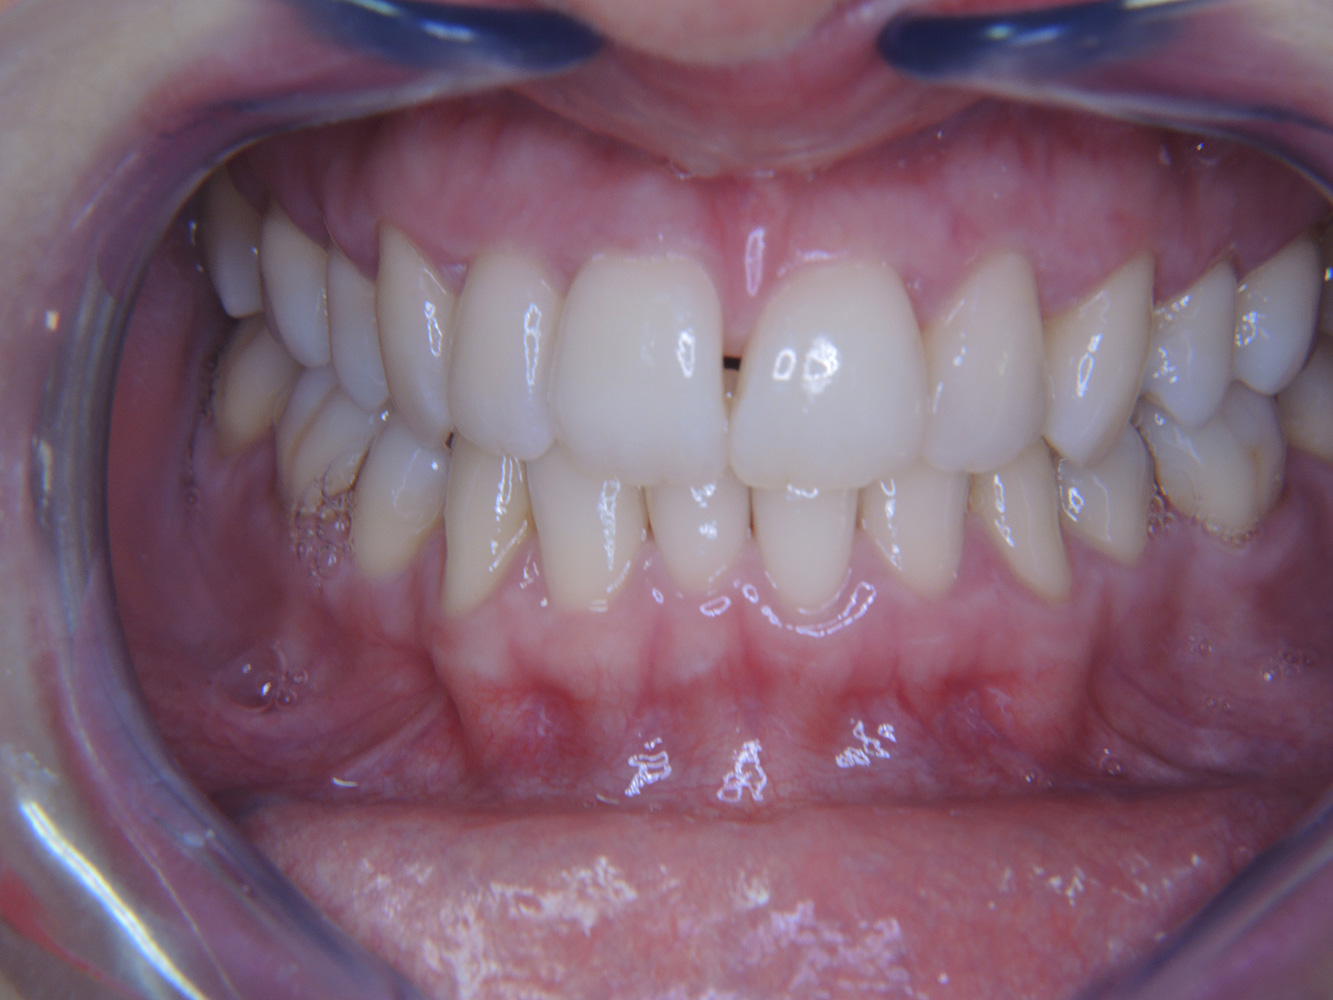

Casi di pazienti secondo l'IPCI seguenti studi di casi servono a mostrare l'interazione tra i fattori di bisogno e di rischio definiti per l'IPC così come gli effetti dei singoli fattori*. La paziente diabetica con una buona igiene oraleUna paziente diabetica di 51 anni con una buona igiene orale si presenta per una seduta di prevenzione. I valori di glicemia sono stabili con HbA1c = 6,2%, per cui si ritiene che la sua condizione possa essere sufficientemente gestita con la metformina (un farmaco per il trattamento del diabete). La paziente non presenta restauri esistenti o precedenti patologie orali. Sulla base dei referti disponibili si può constatare una gengivite nonostante una condizione altrimenti stabile. di più Case presentation: Complex Dental Prosthesis ManagementThe direct relationship between intraoral and general health, as well as the bidirectional influence that they may have on one another, is well-known (1,2). It is absolutely essential to consider both factors when planning preventive intraoral measures and treatment in the dental practice. The primary objective is the maintenance of patient health and quality of life from both dental and medical perspectives. more The (orally) healthy patient with implantsIn the medical history, the 55-year-old patient states that he has no systemic disease and is not taking any medication. The patient’s lifestyle is similarly unremarkable. The patient has a few tooth restorations and two implants (2nd and 4th quadrants). On the basis of current findings, gingivitis is identified in an otherwise stable periodontal condition on the reduced periodontium (stage III, grade A). more The healthy patient with pre-existing periodontal disease & peri-implantitisA 52-year-old patient presents at a preventive care session. The patient has no systemic disease and is not taking any medication. He has had various dental treatments and also has two active carious lesions. In addition, the patient has four implants (2nd, 3rd and 4th quadrants). He is revealed to have early periodontal disease (stage IV, grade B). His periodontal condition is stable; a probing depth of Probing depths (ST) of 5 mm is only evident at the implant in region 36. Gingivitis is also identified. more The Diabetic Patient with Pre-Existing PeriodontitisThis case report of a 52-year-old male with type 2 diabetes and periodontitis emphasizes personalized preventive measures and periodontal health maintenance to manage the moderate disease progression risk. more The 28-Year-Old Cigarette Smoker with Dental Erosions28-year-old patient, smoker, with erosions. The bidirectional relationship between oral and general medical health is very well known. It is no longer sufficient – and arguably even old-fashioned – to consider intraoral conditions in isolation. In order to create a personalized, case-specific preventive and patient profile, it is essential to take a detailed medical history and perform diligent examination of the general medical and intraoral health, as well as considering the two in combination. more Il paziente affetto da endocardite con lesioni cariose attiveIl paziente ha 39 anni e in passato è stato sottoposto ad un intervento per la sostituzione della valvola aortica dovuta a insufficienza valvolare ed endocardite. Assume regolarmente l'ASS 100 come anticoagulante. Per quel che riguarda lo stile di vita, il regime alimentare seguito dal paziente è classificato come “dieta che favorisce la formazione della carie”, per via del consumo regolare di cibi ad alto contenuto di zuccheri e dei sei-sette pasti consumati al giorno. La salute orale del paziente indica un rischio moderato di carie, con lesioni attive. Il rischio di parodontite è basso, tuttavia il paziente è affetto da gengivite. Si formulano quindi i seguenti consigli per il trattamento di profilassi. di più Il paziente trapiantato con iperplasia gengivaleSi presenta un paziente di 71 anni che ha subito un trapianto di reni e con anamnesi di ipertonia (ipertensione). Considerata la sua storia clinica, serve una terapia a lungo termine con ciclosporina che ha un effetto immunosoppressivo e amlodipina che è specifica contro l'ipertensione. Il paziente riporta anche gengive sensibili e sanguinanti. Per quanto riguarda invece lo stato di salute orale, il paziente ha un restauro, presenta un'iperplasia gengivale marcata, una parodontite allo stadio II, grado B con tasche attive e un'iniziale carie radicolare al dente 22 e in più mancano otto denti. Dalla valutazione del rischio di carie si evince un rischio moderato di carie (API 60). Per la seduta di profilassi si possono formulare i seguenti consigli per il trattamento. di più La paziente sana con precedente patologia parodontaleQuesta paziente di 68 anni non presenta alcuna patologia precedente né segue alcuna terapia che possano ritenersi rilevanti dal punto di vista odontoiatrico, e il suo stile di vita non comporta alcun rischio particolare. La paziente ha due impianti (3° quadrante, da cinque anni) e una precedente patologia parodontale (parodontite allo stadio IV, grado B) con perdita del dente. Al momento le condizioni parodontali sono stabili, tuttavia la parodontite aumenta in misura significativa le complicazioni biologiche degli impianti e c'è dunque il rischio di perdita dell'impianto (21). Per la seduta di profilassi si possono formulare quattro consigli. di più